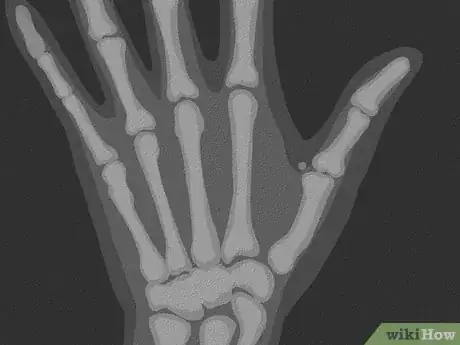

3Get an x-ray taken of your thumb. The doctor will likely order x-rays of your thumb from a variety of angles.[14] This will not only confirm their diagnosis, but it will also show the doctor exactly how many fractures your thumb has sustained, which will assist in determining the best treatment option. The angles for the x-rays include:[15]

- Lateral: The lateral view is an x-ray with the hand resting on its side, so that the thumb is up.

- Oblique: The oblique view is an x-ray with the hand tilted, resting on its side, so that the thumb is up.

- AP: The AP view is an x-ray of your hand in a flattened position, from above.